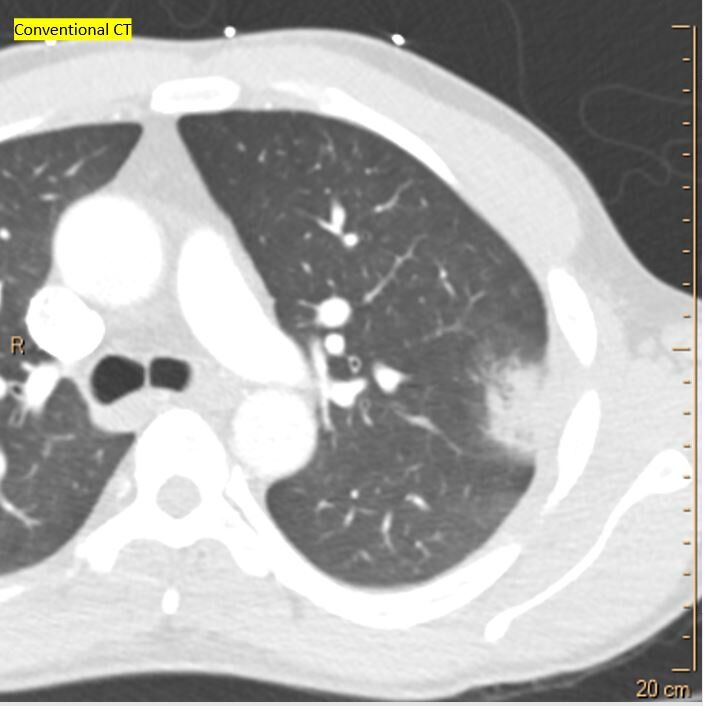

Conventional CT shows pleural thickening